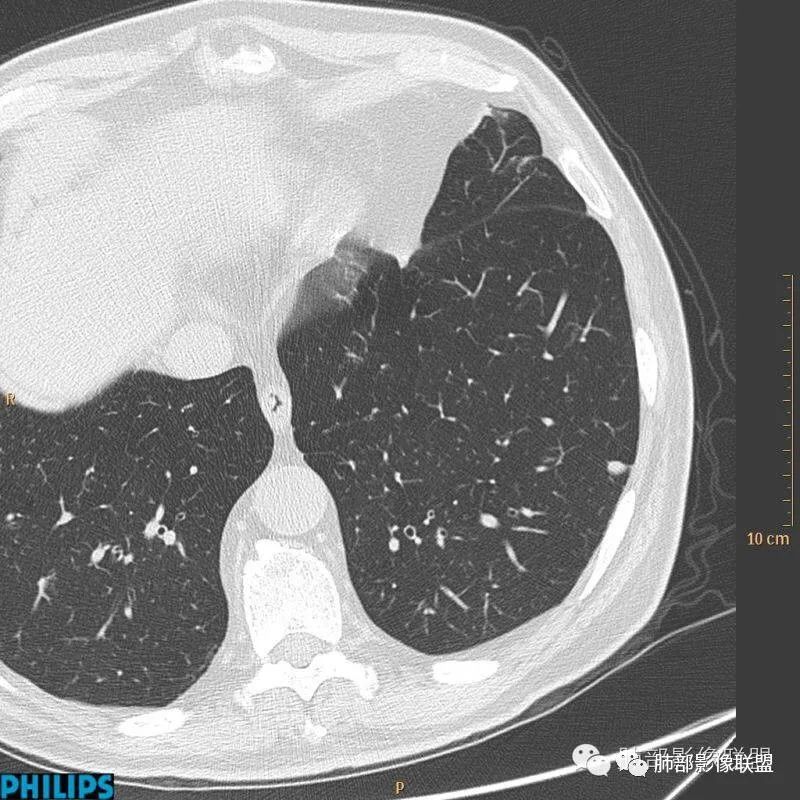

病例三:

以上病例,有什么共同点?1、病灶均位于胸膜下或叶间胸膜下;

2、病灶边缘多平直,大部分呈三角形,部分呈椭圆形;

3、病灶边缘见一条或数条细线与胸膜相连。

正常情况下,肺内淋巴结是不显示的,一般是慢性炎症所致,老年人和吸烟者多见。影像上常见于胸膜或叶间胸膜下,迄今为止,所有的报道均距胸膜或叶间胸膜小于2.0cm以内。也可以表现为与胸膜或叶间胸膜相贴的结节。绝大多数位于中下叶(气管隆突水平以下),上叶也可见到,但较少见。

长径均小于12mm。典型的形状为三角形,也可以为梭形、圆形或椭圆形。诊断的关键在于见到1-5条细线与胸膜、叶间胸膜或静脉相连,有时状如坐落于电路板的“二极管”,但以薄层CT显示为佳。有作者病理对照线状影为小叶间隔,有作者病理对照为淋巴管。其实不矛盾,因为淋巴管走行于小叶间隔内。

需要与小肺癌、肺转移瘤进行鉴别。肺内淋巴结除细线状影外,边缘清晰无分叶,无毛刺,没有磨玻璃晕,少张力等是与肺癌鉴别的关键。有作者对9例胸膜下的小于1cm的肺转移瘤进行对照,后者均为较为游离的类圆形,无线状影与胸膜或肺静脉相连。